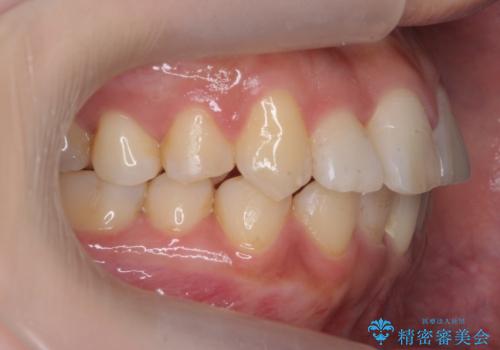

- 前歯のがたつき、受け口を主訴に来院。

上の前歯が二本裏側に入っていました。(反対咬合といいます)

上はワイヤー部分矯正、下はインビザライン(マウスピース)で部分矯正を行いました。

上の前歯のデコボコは激しく、かぶせ物で治療するとなると2本抜歯してブリッジになってしまいます。ダミーの歯の大きさも小さくなるため不自然になり下の歯のがたつきもあるためお勧めできません。